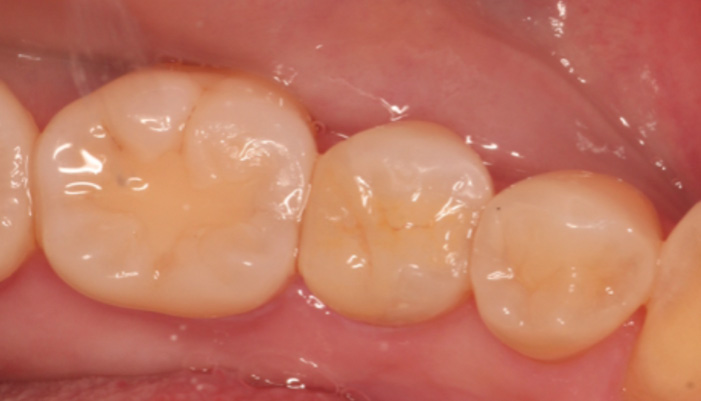

治療後

患者様は「何度も腫れる」「根の治療を繰り返している」とのお悩みで来院されました。診査の結果、歯の根の先に膿の袋(根尖病変)が確認され、過去の治療で細菌が十分に取り除けていない可能性が考えられました。そこで、ラバーダムを使用して治療部位への細菌の侵入を防ぎながら、拡大視野下で精密な根管治療の再治療を行い、感染源の徹底的な除去を行いました。

| 主訴 | 右下が腫れて痛い |

|---|---|

| 治療期間 | 1ヶ月 |

| 治療費 | 保険適用 |

| 治療内容 | レントゲンで確認すると、根尖病変が認められ根管治療を行いました。 |

| 治療のリスク | 再発が起きる場合は、外科処置を追加で必要なケースがあります。 |